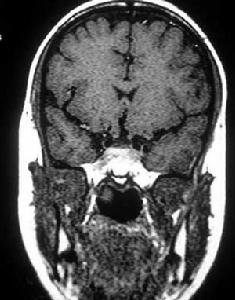

臨床表現為視力視野障礙,影像學檢查可見鞍區病變,蝶鞍骨質變化。如有內分泌表現診斷一般不難,需和顱咽管瘤、腦膜瘤、動脈瘤等鑑別,MRI對發現微腺瘤很有意義。

垂體瘤診斷方面,影像學檢查是非常重要的手段。其中以鞍區的核磁共振(MRI)檢查對垂體瘤的檢出率最高。通過鞍區薄層(每1mm掃描一層)增強影像的MRI檢測,若結合動態造影MRI檢測,直徑小至2-3mm的垂體微腺瘤也可以顯像。鞍區增強CT顯像對於部分垂體大腺瘤顯像效果好,可以了解鞍底骨質的破壞程度以及蝶竇氣化的程度。